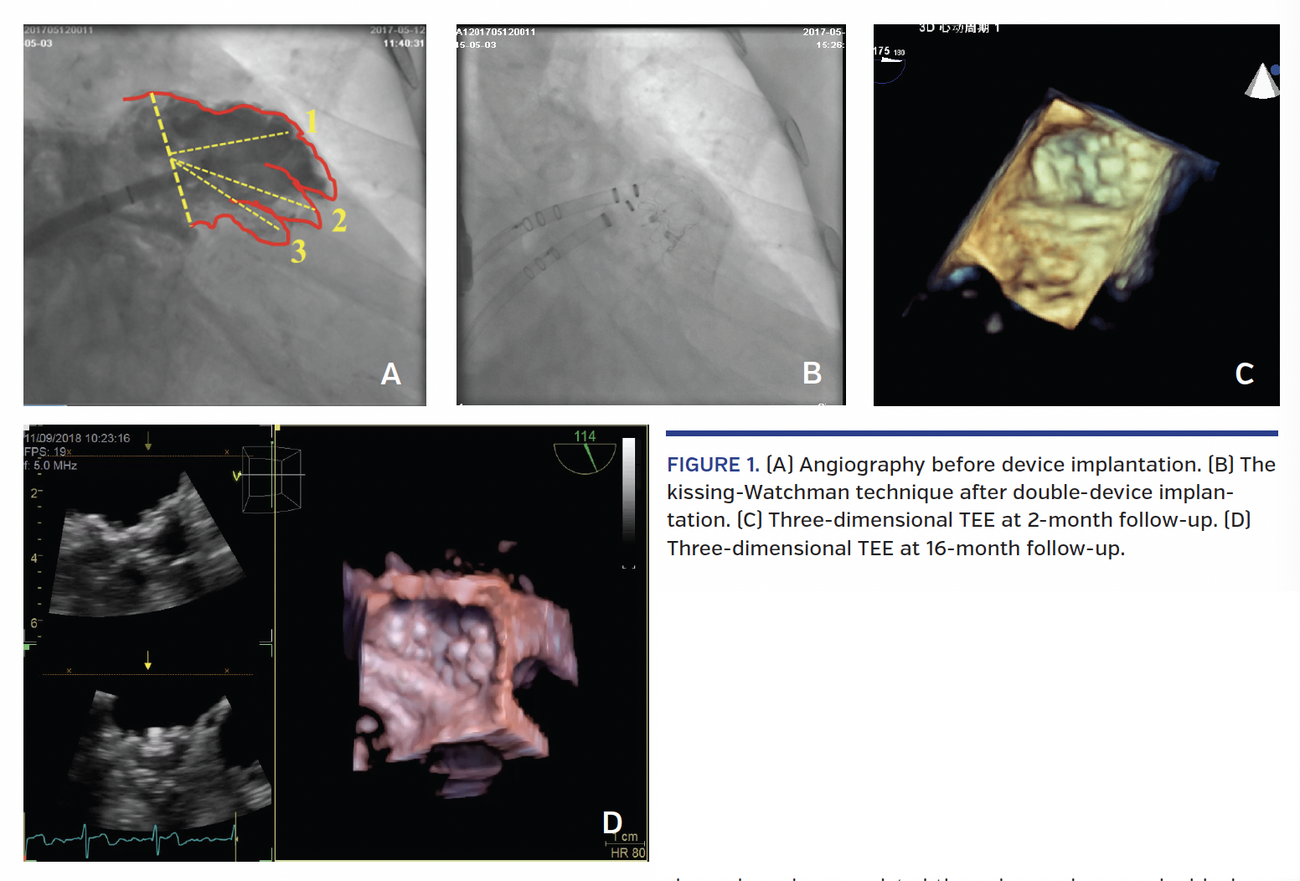

Transesophageal echocardiography (TEE) showed a large-ostium, 26 x 31 mm LAA; angiography showed a cactus morphology with 3 early outgoing lobes (Figure 1A). A significant residual leak persisted after we chose the upper lobe as the landing zone for a 33 mm Watchman device (Boston Scientific). We then tried to repeatedly deploy the Watchman in the medium or lower lobe zones, but significant residual leakage still persisted. Therefore, we planned to close the LAA with a kissing-Watchman technique. First, a 27 mm Watchman was anchored in the upper lobe, and pull test was performed to ensure stabilization. Transesophageal echocardiography (TEE) showed a 16 mm residual leakage in the lower lobe, so a 21 mm Watchman was placed next to the first device (Figure 1B). The tug-test was performed on both devices; TEE showed no residual leaks. Postprocedure TEE 2 months later showed a 2 mm residual leak between the devices (Figure 1C), while TEE at 16-month follow-up showed no device-related thrombus and no residual leakage (Figure 1D). Warfarin was prescribed for the first 2 months, and dual-antiplatelet therapy (aspirin 100 mg/day and clopidogrel 75 mg/day) was given until 12 months; aspirin 100 mg/day was then prescribed indefinitely.